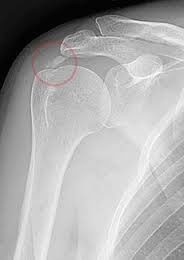

Εικόνα με ακτινογραφία ώμου στην οποία εμφανίζεται η ασβεστοποίηση.

Πως γίνεται η διάγνωση της ασβεστοποίησης του ώμου;

Η διάγνωση, γίνεται κλινικά και επιβεβαιώνεται με ακτινολογικό έλεγχο, ενώ σημαντικές πληροφορίες προσφέρουν τόσο το υπερηχογράφημα, όσο

και η μαγνητική τομογραφία (MRI) για ανακάλυψη συνοδών βλαβών του ώμου όπως εκφυλίσεις και ρήξεις τενόντων.